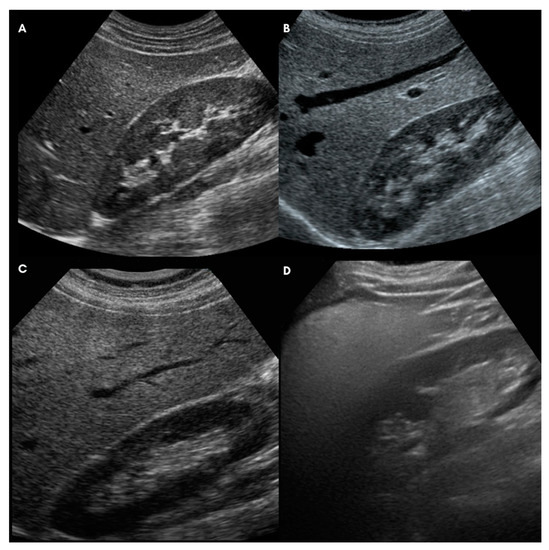

3.3. Liver Enzymes, Scores and US Appearance of NAFLD

- Ferraioli, G.; Monteiro, L.B.S. Ultrasound-Based Techniques for the Diagnosis of Liver Steatosis. World J. Gastroenterol. 2019, 25, 6053–6062. [Google Scholar] [CrossRef]

- Hamaguchi, M.; Kojima, T.; Itoh, Y.; Harano, Y.; Fujii, K.; Nakajima, T.; Kato, T.; Takeda, N.; Okuda, J.; Ida, K.; et al. The Severity of Ultrasonographic Findings in Nonalcoholic Fatty Liver Disease Reflects the Metabolic Syndrome and Visceral Fat Accumulation. Am. J. Gastroenterol. 2007, 102, 2708–2715. [Google Scholar] [CrossRef]

| Ultrasound-Liver Steatosis Score (modified from Hamaguchi et al. 2007) [36] |

| A. Bright liver and hepatorenal echo contrast |

| 0: Bright liver and hepatorenal US contrast are negative |

| 1: Bright liver and/or hepatorenal US contrast are slightly positive |

| 2: Bright liver and/or hepatorenal US contrast are mildly positive |

| 3: Bright liver and/or hepatorenal US contrast are strongly positive |

| B. Deep attenuation |

| 0: Deep attenuation is completely negative |

| 1: Deep attenuation is mild (the deep parts of the liver are visualized but appear hypoechoic) |

| 2: Deep attenuation is severe (the diaphragm, but not the deep liver parenchyma, can be distinguished) |

| 3: Total barrage of the ultrasound beam (neither deep liver parenchyma nor diaphragm can be distinguished) |

| C: Vessel blurring |

| 0: Vessel blurring is negative |

| 1: The borders of intrahepatic vessels are not perfectly defined |

| 2: The border of intrahepatic vessels is mildly unclear or the lumen of intrahepatic vessels is narrowed |

| 3: Intrahepatic vessels are not visible (“featureless liver”) |

| D: Parenchymal US-pattern |

| 0: Parenchymal US-pattern is homogeneous |

| 1: Parenchymal US-pattern is slightly inhomogeneous |

| 2: Parenchymal US-pattern is mildly inhomogeneous |

| 3: Parenchymal US-pattern is severely inhomogeneous. |

| Ultrasound Steatosis Score (0–12) = A + B + C + D |